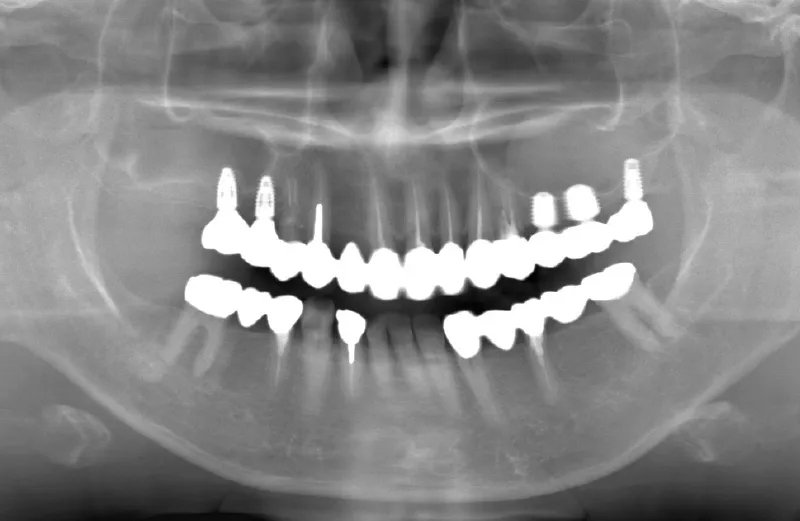

メガジェンオペの症例紹介01

治療前

治療後

| 主訴 | 入れ歯は以前に入れたことがあるが違和感が強く入れられなかったので右上左上をインプラントで治療して欲しい。 左上は他院では上顎洞までの垂直骨量が1mm程度しかないのでサイナスリフトが必須であり、インプラント治療で歯が入るまでに1年以上かかると言われたのでセカンドオピニオンを希望で来院。 |

|---|---|

| 治療期間 | 右上は2.5ヶ月、左上は3.5ヶ月で仮歯が入り、 4.5ヶ月で最終補綴物が入って終了。 |

| 治療費 | 約2,300,000円 |

| 治療内容 | エクストラワイドショートインプラントを埋入し、上顎洞を移植材を用いずに挙上しインプラントを埋入した。仮歯を装着し、様々な機能面に問題がないことを確認し4.5ヶ月で最終補綴物を装着して終了した。 |

| 治療の リスク |

インプラント埋入オペ時に術者が上顎洞内にインプラントを迷入させる可能性がある。これは術者が技術的に熟練していれば防ぐことが可能。 |